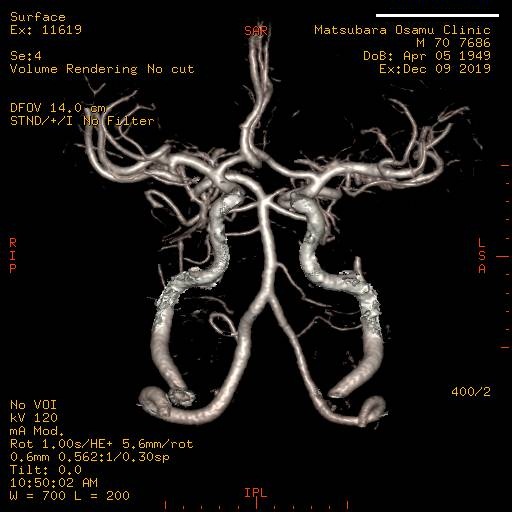

検査の内容によっては、色々な角度からの断面図や3D画像を作ることもできます。撮影部位を変えることで様々な画像を得ることができます。

造影剤を使用することにより、血管3D画像を作成することも可能になります。